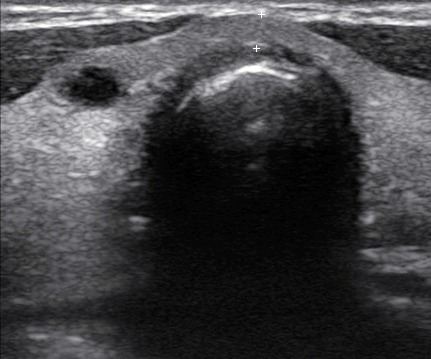

Bazo aumentado de tamaño (16 cm) con abundantes imagenes hipoecogénicas heterogéneas, de bordes mal definidos, no vascularizadas, que no dejan refuerzo; en el corte transversal se aprecia una imagen hiperecoica en polo superior.

En hilio esplénico se observan imagenes hipoecoicas redondeadas de bordes bien definidos, no vascularizadas, sugerentes de adenopatias.